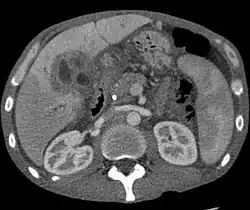

Ultrasound of the liver and biliary tree is often used as the initial imaging modality in people with suspected obstructive jaundice.[50][51] Ultrasound can identify obstruction and ductal dilatation and, in some cases, may be sufficient to diagnose cholangiocarcinoma.[52] Computed tomography (CT) scanning may also play an important role in the diagnosis of cholangiocarcinoma.[53][54][55]